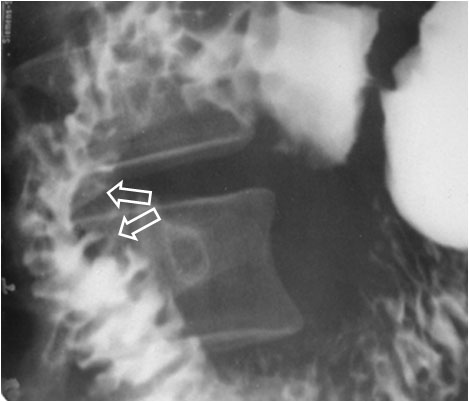

SIGNO DEL TRES INVERTIDO o DE FROSTBERG

Signo de crecimiento de la cabeza pancreática (por carcinoma, pancreatitis, etc) en el estudio baritado. La parte central del 3 corresponde a la zona de fijación de la pared duodenal, donde está la papila. Las dos impresiones por encima y por debajo de este punto (flechas) corresponden al crecimiento pancreático, asociado al edema o infiltración de la pared duodenal (que puede ocasionar pérdida de pliegues en ésta). También se ha descrito en el carcinoma duodenal.

Esta imagen corresponde a un paciente con carcinoma pancreático.

El signo también se conoce como Signo de Frostberg o Signo del 3 invertido de Frostberg.

Otro ejemplo de este signo en un paciente con pancreatitis.